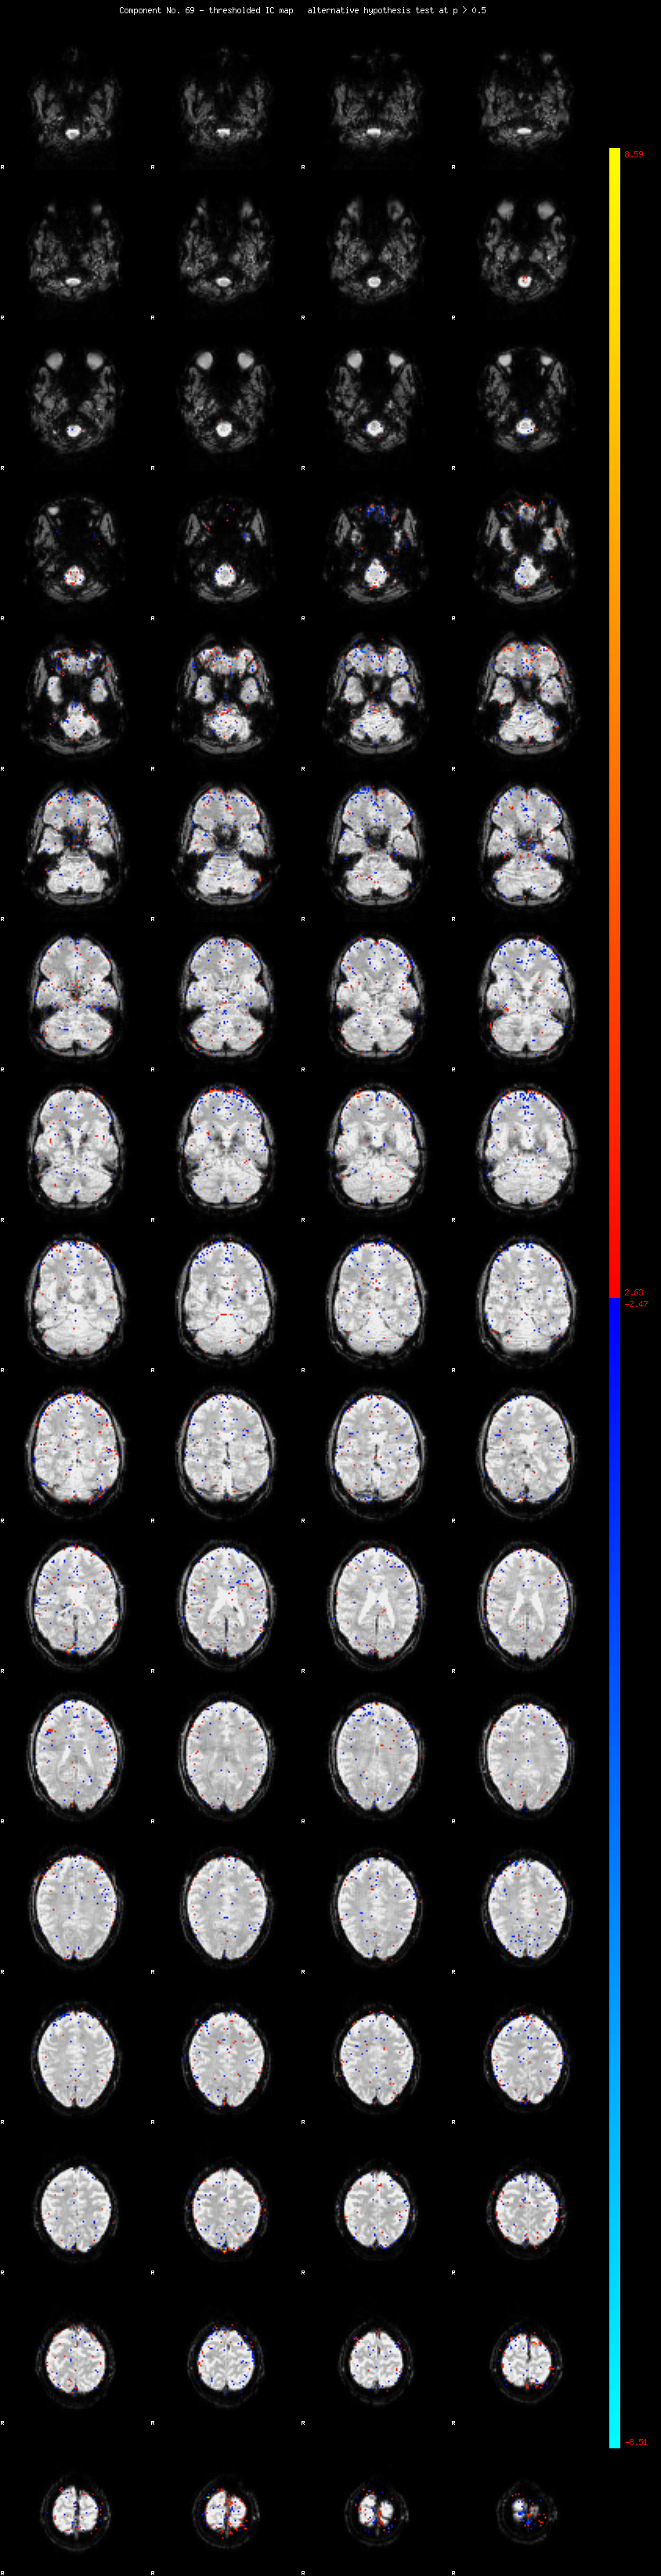

MELODIC Component 69

0.78 % of explained variance;     0.51 % of total variance

MMfit